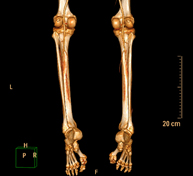

- Lower leg rotational study using CT [patella, tibial tuberosity to trochlear groove (TT-TG) distance]

Radiological examination based on an X-ray system and detectors that rotate around the patient, reconstructing the images by computer (multidetector computed tomography - MDCT) to calculate a series of measurements at the hips, knees and ankles with a view to solving problems affecting the rotation and angulation of the lower limbs.

- TC Huesos largos

Exploración radiológica que mediante un sistema de rayos X y detectores que giran alrededor del paciente, reconstruyendo las imágenes por ordenador (TC Multidetector), permite el estudio de huesos largos (tibia, peroné, fémur, húmero, radio y cúbito). - Biopsia ósea guiada por TC